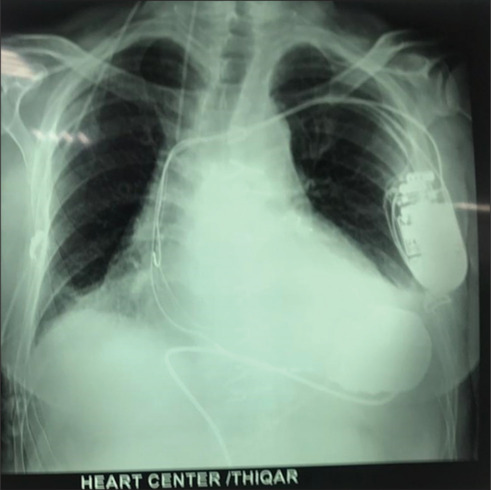

The first successful implantation of the HeartMate 3 LVAD in Iraq represents a transformative achievement in the nation's medical history. Conducted collaboratively by German and Iraqi teams in December 2023, the procedure addressed end-stage heart failure in a 60-year-old male. Despite significant healthcare challenges, the patient's functional status improved markedly, moving from New York Heart Association Class IV to Class I within a year. This groundbreaking case highlights the potential for Iraq to integrate advanced cardiac interventions into its healthcare system, paving the way for heart transplantation programs. Ongoing collaboration and investment in healthcare infrastructure will be pivotal for sustaining these innovations.